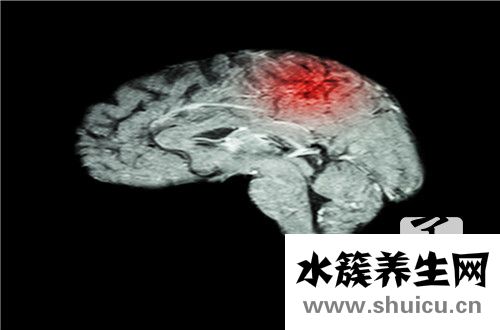

透射电镜下由此可见肌膜下或肌原纤维间很多膜蛋白堆积,膜蛋白的尺寸和形状显著出现异常,膜蛋白嵴内出現晶格常数状包涵体,排成地下停车场样构造。除此之外,膜蛋白嵴可呈板层样或内切圆样排序,后面一种外型似“树轮”状。脑的基本病理学改变为脑组织呈蜂窝状,神经细胞退行性病变,脑组织出現灶区坏死,星型胶质细胞增生,继发性髓鞘脱落及其基底核铁制堆积等。